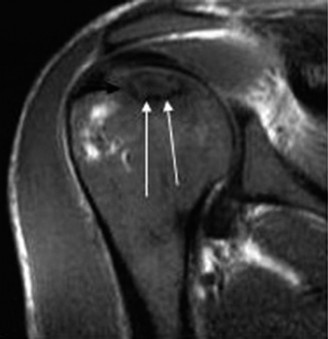

Magnetic Resonance Imaging (MRI), particularly without contrast or as an MR Arthrogram (MRA), remains the gold standard for evaluating the soft tissue envelope of the shoulder. For partial-thickness tears, MRI provides exquisite detail regarding the location (articular-sided, bursal-sided, or interstitial) and the depth of the tear. A T2-weighted coronal oblique sequence will typically demonstrate a focal region of hyperintensity extending partially through the tendon substance. Articular-sided partial tears (PASTA lesions - Partial Articular Sided Tendon Avulsions) are the most common and are best visualized on MRA, where the gadolinium contrast will imbibe into the articular defect, sharply outlining the extent of the avulsion from the footprint.

When templating for surgery, the orthopedic surgeon relies heavily on the Ellman Classification of partial-thickness rotator cuff tears. Ellman categorizes tears based on their location (A = Articular, B = Bursal, C = Interstitial) and their depth relative to the normal tendon thickness (which is approximately 10-12 mm at the footprint). Grade I tears involve less than 3 mm of depth (<25% of tendon thickness). Grade II tears involve 3 to 6 mm of depth (25-50% of tendon thickness). Grade III tears involve greater than 6 mm of depth (>50% of tendon thickness). This classification is not merely academic; it drives the intraoperative decision-making algorithm.

Conversely, for Ellman Grade III tears (greater than 50% thickness), the remaining tendon is considered biomechanically compromised and at high risk for progression to a full-thickness tear. In these scenarios, the surgeon must decide between two primary repair techniques: an in situ transtendon repair or a formal takedown and repair. A takedown involves completing the tear to a full-thickness defect and repairing it using standard techniques. While this provides excellent visualization, it sacrifices the remaining intact, healthy tendon fibers. The in situ repair preserves the intact bursal or articular fibers, theoretically maintaining the native biomechanical length-tension relationship, but is technically more demanding.